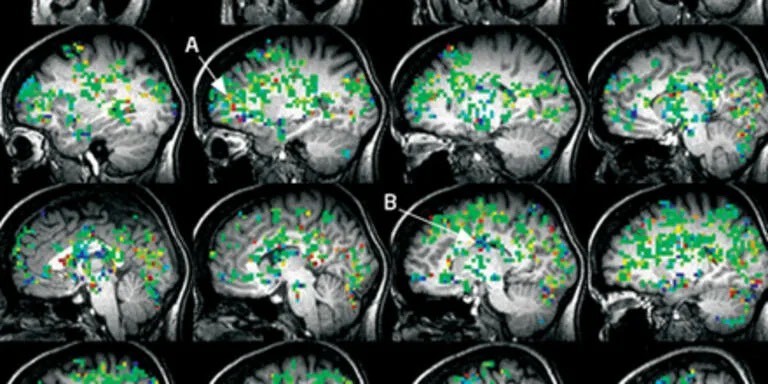

Изменения, происходящие в организме во время оргазма, охватывают головной мозг. Американский исследователь профессор-психолог Barri Komisaruk (Барри Комисарук), который работает на кафедре психологии университета Рутджерс в Нью-Джерси, с 1960 г. изучает феномен оргазма.

«Что происходит в мозге во время оргазма?»

Хотя причин для занятия сексом очень много, они разнообразны , однако, конечная цель – это достижение оргазма. Но из-за того, что все мы такие разные, создать универсальное описание оргазма невозможно. Единственное, что объединяет людей при описании того, что они испытывают во время ...